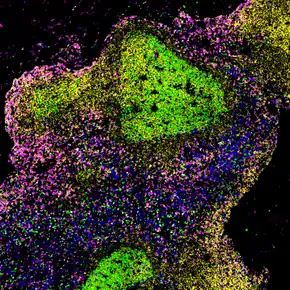

Benign lymphadenopathy is a common biopsy finding, and may often be confused with malignant lymphoma. It may be separated into major morphologic patterns, each with its own differential diagnosis with certain types of lymphoma. Most cases of reactive follicular hyperplasia are easy to diagnose, but some cases may be confused with follicular lymphoma. There are seven distinct patterns of benign lymphadenopathy:[7]

- Follicular hyperplasia: This is the most common type of reactive lymphadenopathy.[7]

- Paracortical hyperplasia/Interfollicular hyperplasia: It is seen in viral infections, skin diseases, and nonspecific reactions.

- Sinus histiocytosis: It is seen in lymph nodes draining limbs, inflammatory lesions, and malignancies.

- Nodal extensive necrosis

- Nodal granulomatous inflammation

- Nodal extensive fibrosis (Connective tissue framework)

- Nodal deposition of interstitial substance

These morphological patterns are never pure. Thus, reactive follicular hyperplasia can have a component of paracortical hyperplasia. However, this distinction is important for the differential diagnosis of the cause.